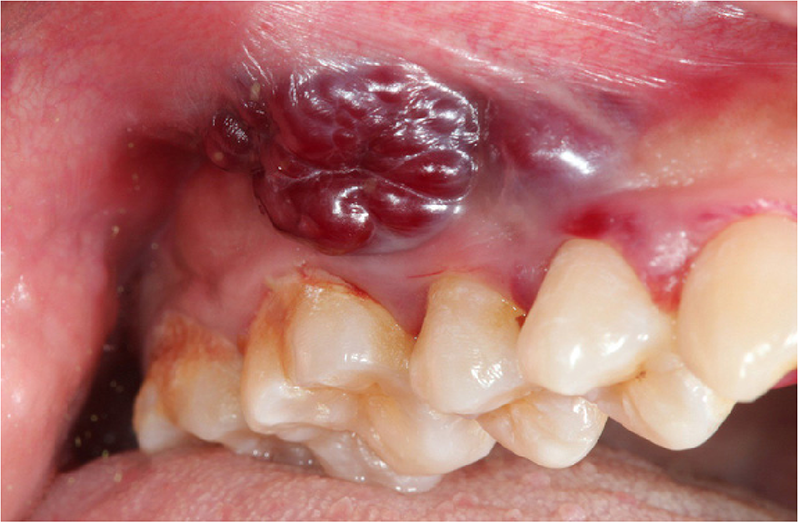

Xuất hiện khối u ở vùng môi hoặc trong toàn bộ khoang miệng, cổ họng cũng là một dấu hiệu của ung thư môi bạn cần lưu ý. Ảnh: dkn.